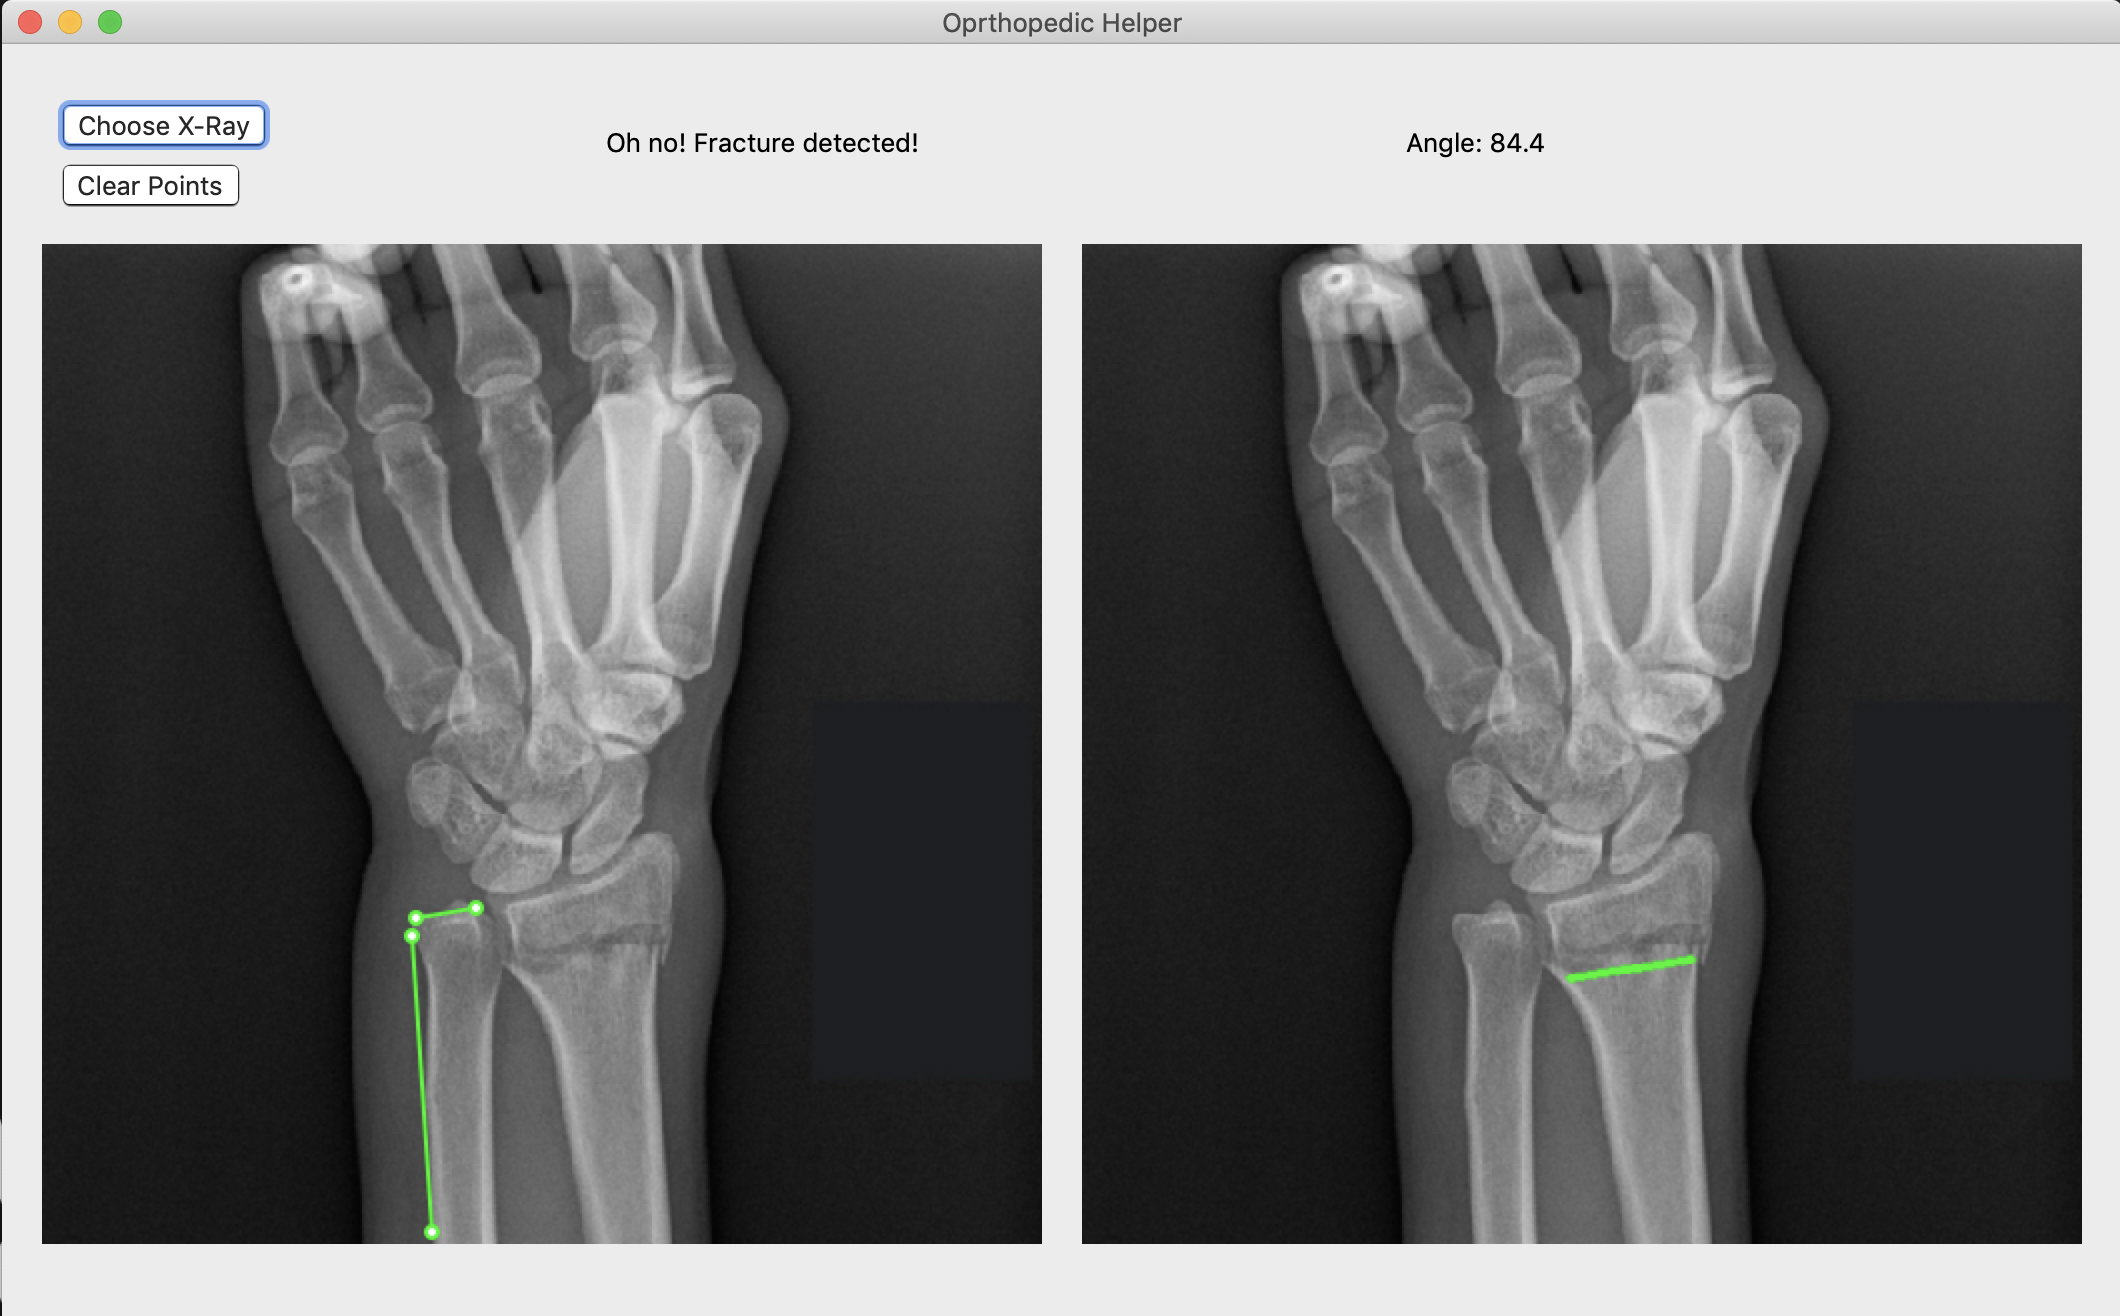

Broke Detector is a simple tool to help analyze the site of wrist injury. It helps doctors decide a) whether the bones are broken or not (which is admittedly very simple for humans, but not for computers) and b) provides tools such as a protractor to provide an objective measurement of how misaligned bones are. Broke Detector aims not to replace the orthopedist, but to aid them.

The actual detection algorithm is the guts of this project (no machine learning involved). The process is as follows: Thresholding: Reasons for this will be listed in the next section, we did this using color histograms to determine the percentile of certain pixel values. Edge detection: We used a simple Söbel kernel (however, not the default opencv one) to handle edge detection, as it was simple to detect only horizontal edges. Hough transform: This is the guts of the algorithm, which decides where horizontal lines are in the X-Ray. It sounds dumb, but choosing the lowest isolated horizontal line almost always results in finding the break in the bone. Flask: We developed a locally hosted web application which supports uploading from the computer. The HTML formatted site displays the results of the Python calculations.

Another challenge with this project was that the GUI framework we went with, wxPython is not only slow but antiquated in terms of GUI design. Something as simple as drawing lines on an image proved to be an immense challenge of trudging through documentation to find the obscure function call that enables something that should be the default anyway.